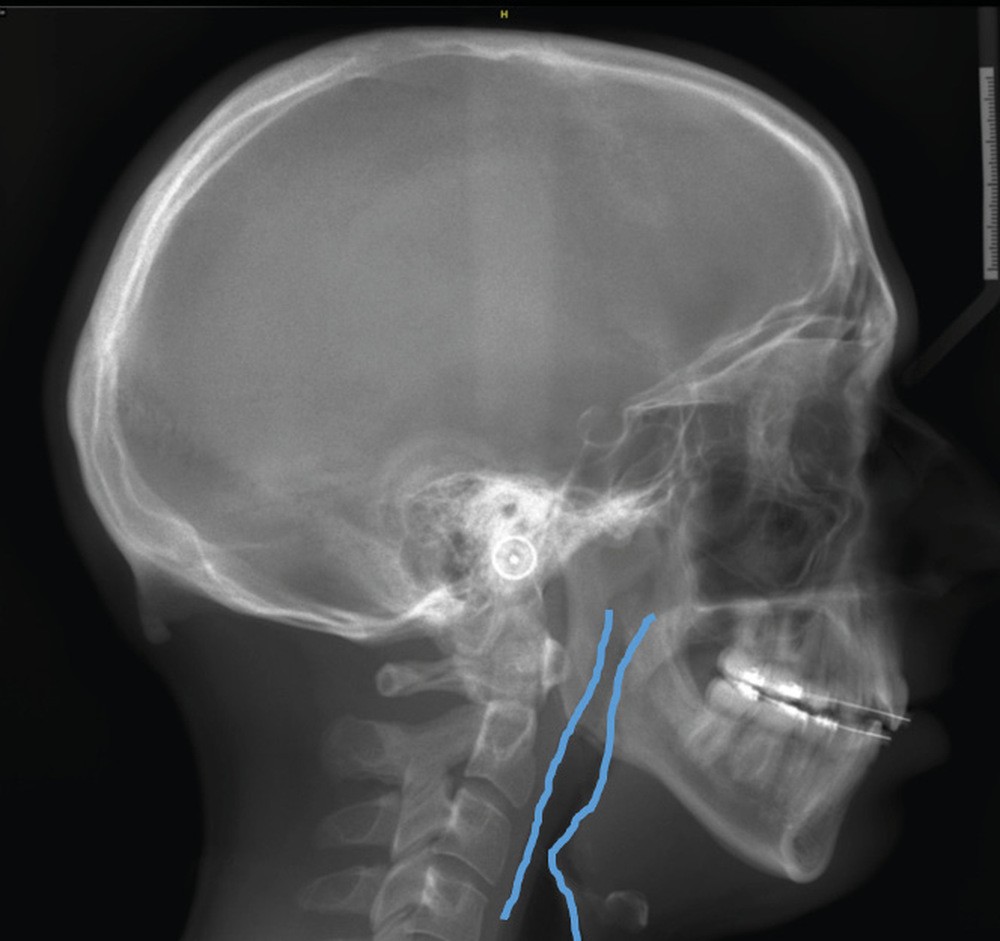

Le Dr François Cheynet et à nouveau le Pr Michel Le Gall (fig. 12) viendront plaider pour une prise en charge chirurgicale précoce de certains décalages squelettiques, afin de briser au plus vite la spirale dysmorpho-dysfonctionnelle et influencer le schéma de croissance postopératoire.

Le Pr Pierre Bouletreau nous rappellera le rôle de chacun des participants à une Réunion de concertation pluridisciplinaire (RCP) du Syndrome d’apnées hypopnées obstructives du sommeil (SAHOS) et insistera sur les dernières indications et contre-indications des orthèses d’avancée mandibulaire et de la chirurgie d’avancée maxillo-mandibulaire (fig. 14a-b).